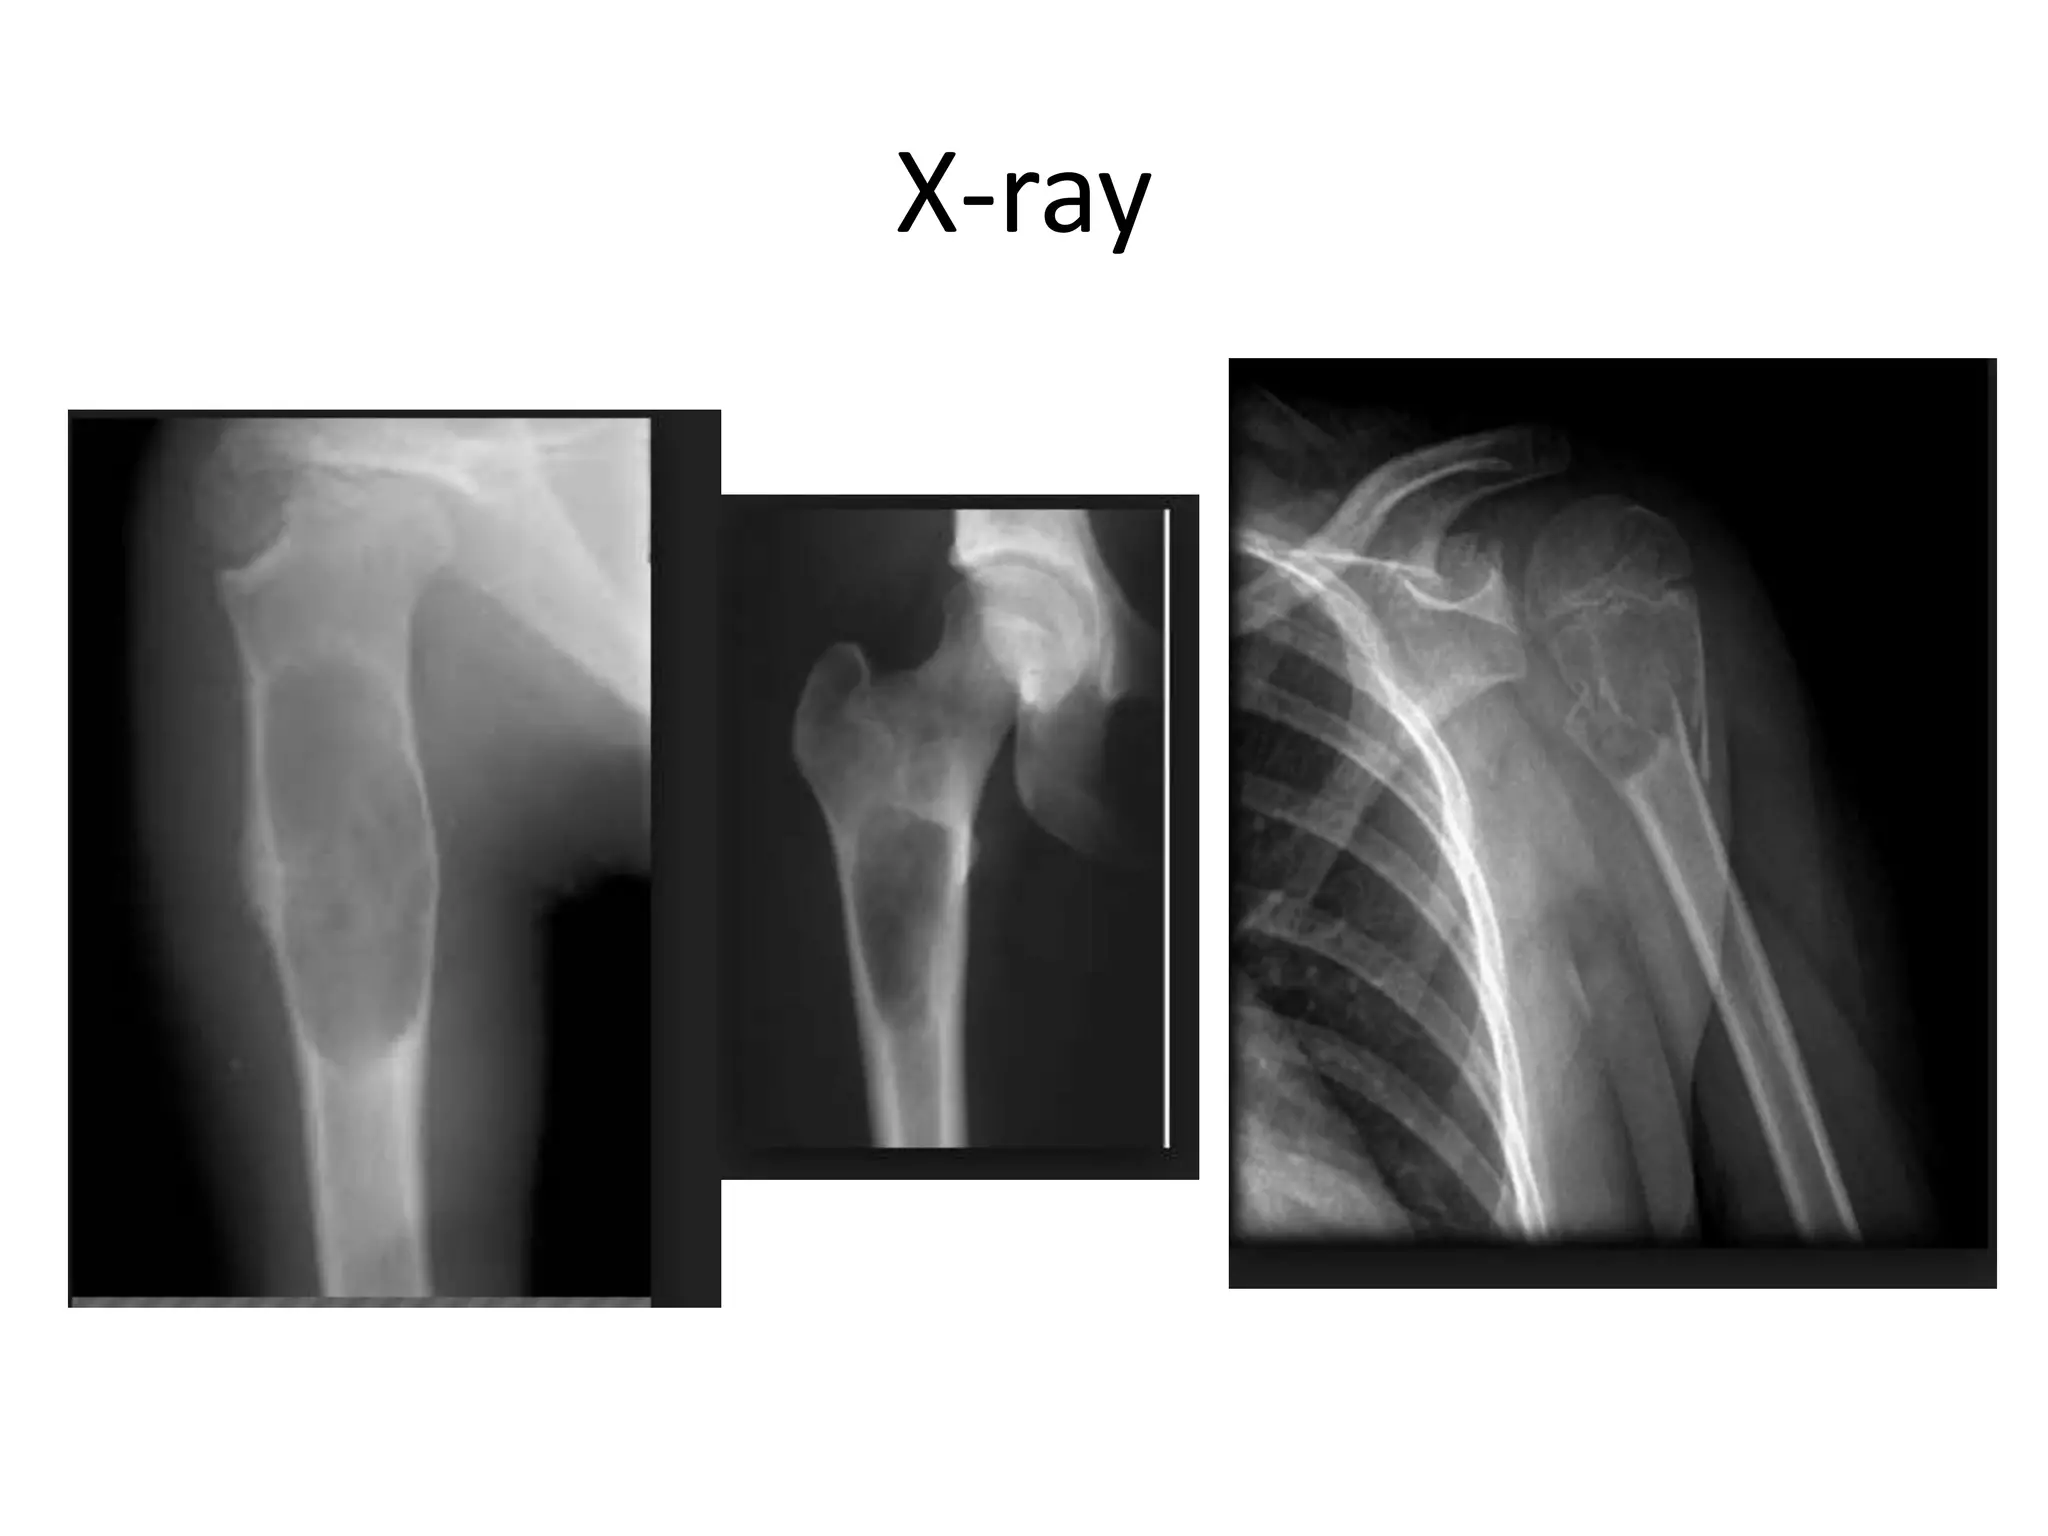

OSTEOCHONDROMA

• Common benign bone tumors

• The lesions consist of a bony mass, often in the

form of a stalk, produced by progressive

endochondral ossification of a growing

cartilaginous cap.

• Common sites- distal femur, the proximal tibia,

and proximal humerus

• Osteochondromas are of two types: pedunculated

and broad based or sessile.

• Solitary Osteochondroma

• Multiple Hereditary Exostoses

• Malignant transformation may occur

• Treatment : osteochondromas may

spontaneously regress. They are usually treated

by simple excision for cosmetic reasons or

when symptoms of pain, limitation of motion,

or impingement on adjacent structures such as

nerves and blood vessels become clinically

manifest.